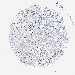

CANCER BREAST CANCER Show tissue menu

BRCA TCGA BRCA VALIDATION PROTEIN EXPRESSION